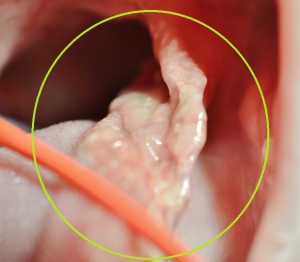

上の写真は写真左側の十二指腸に詰まった異物摘出の最中の写真です。各々が紐のような構造でつながっていました。

取り出した右の「1匹目のネズミ」に絡みついた女性の毛髪その繊維が編み糸のようになって20cmほどのひも状になっており、摘出中の左の「2匹目のネズミ」に絡みついて長い異物となっているのが確認できます。

大変厄介な異物でしたが「2匹のネズミ」を摘出して切開した腸管を縫合して、本来ならば手術が一段落するはずでしたが。。。ここで、またさらに問題が起きました。

どうやら左の十二指腸の「2匹目のネズミ」を摘出する際に別なヒモ状物がさらに上流の胃の中までつながっているのが発見されました。これはつまり、胃の中にに「3つ目の異物」が存在している証拠になります。

胃内での異物の状態が不明なため、手術と同時に口から内視鏡を使って胃内を検査しているところが上の写真です。